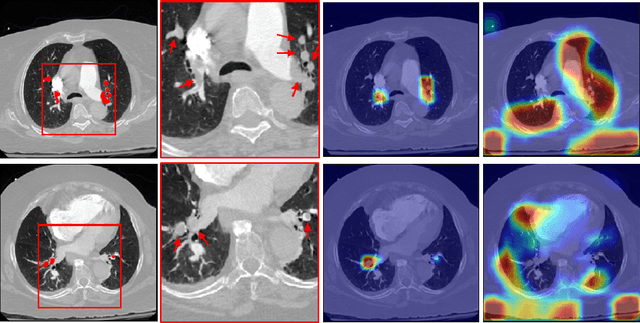

Abstract:Pulmonary Embolism (PE) is a life-threatening disorder associated with high mortality and morbidity. Prompt diagnosis and immediate initiation of therapeutic action is important. We explored a deep learning model to detect PE on volumetric contrast-enhanced chest CT scans using a 2-stage training strategy. First, a residual convolutional neural network (ResNet) was trained using annotated 2D images. In addition to the classification loss, an attention loss was added during training to help the network focus attention on PE. Next, a recurrent network was used to scan sequentially through the features provided by the pre-trained ResNet to detect PE. This combination allows the network to be trained using both a limited and sparse set of pixel-level annotated images and a large number of easily obtainable patient-level image-label pairs. We used 1,670 sparsely annotated studies and more than 10,000 labeled studies in our training. On a test set with 2,160 patient studies, the proposed method achieved an area under the ROC curve (AUC) of 0.812. The proposed framework is also able to provide localized attention maps that indicate possible PE lesions, which could potentially help radiologists accelerate the diagnostic process.

Abstract:Pulmonary embolisms (PE) are known to be one of the leading causes for cardiac-related mortality. Due to inherent variabilities in how PE manifests and the cumbersome nature of manual diagnosis, there is growing interest in leveraging AI tools for detecting PE. In this paper, we build a two-stage detection pipeline that is accurate, computationally efficient, robust to variations in PE types and kernels used for CT reconstruction, and most importantly, does not require dense annotations. Given the challenges in acquiring expert annotations in large-scale datasets, our approach produces state-of-the-art results with very sparse emboli contours (at 10mm slice spacing), while using models with significantly lower number of parameters. We achieve AUC scores of 0.94 on the validation set and 0.85 on the test set of highly severe PEs. Using a large, real-world dataset characterized by complex PE types and patients from multiple hospitals, we present an elaborate empirical study and provide guidelines for designing highly generalizable pipelines.